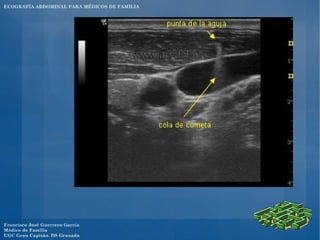

El documento presenta un programa de ecografía abdominal para médicos de familia que incluye presentaciones sobre generalidades de la ecografía y anatomía normal de los órganos abdominales los jueves, y sobre imágenes anormales en ecografía abdominal y ecografía obstétrica los viernes, con un caso clínico el sábado en el centro.